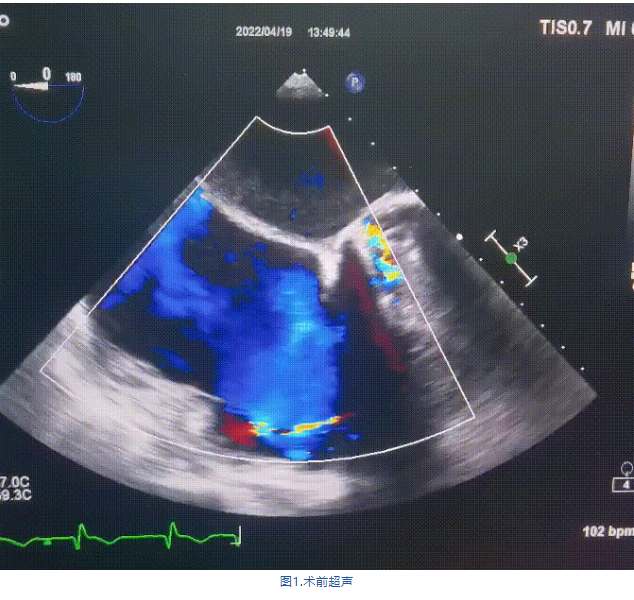

術(shù)前超聲提示:

1.右心、左房明顯增大;

2.二尖瓣人工機(jī)械瓣功能正常,無瓣周漏;

3.三尖瓣環(huán)巨大擴(kuò)張,收縮期瓣葉對(duì)合不攏,收縮期三尖瓣房側(cè)見大量反流信號(hào),反流面積15-20cm²,TRVmax:240cm/s,跨瓣壓差:23 mmHg。